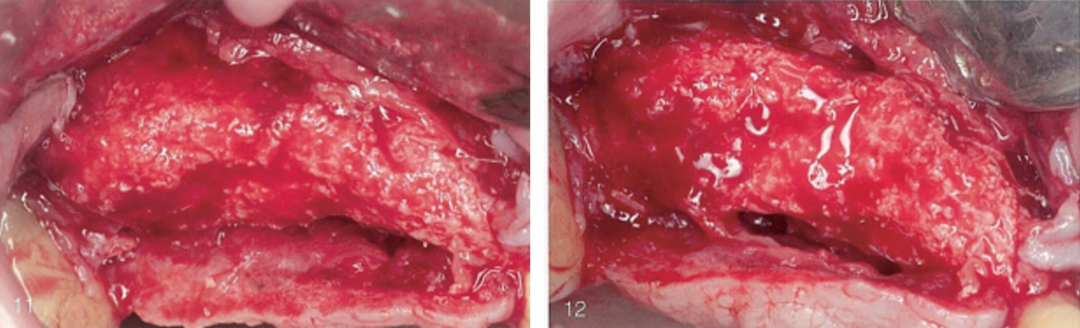

(11)和(12)唇侧观及牙合面观,术区搔刮和冲洗之后,可见牙槽嵴上仍有完整的移植骨。